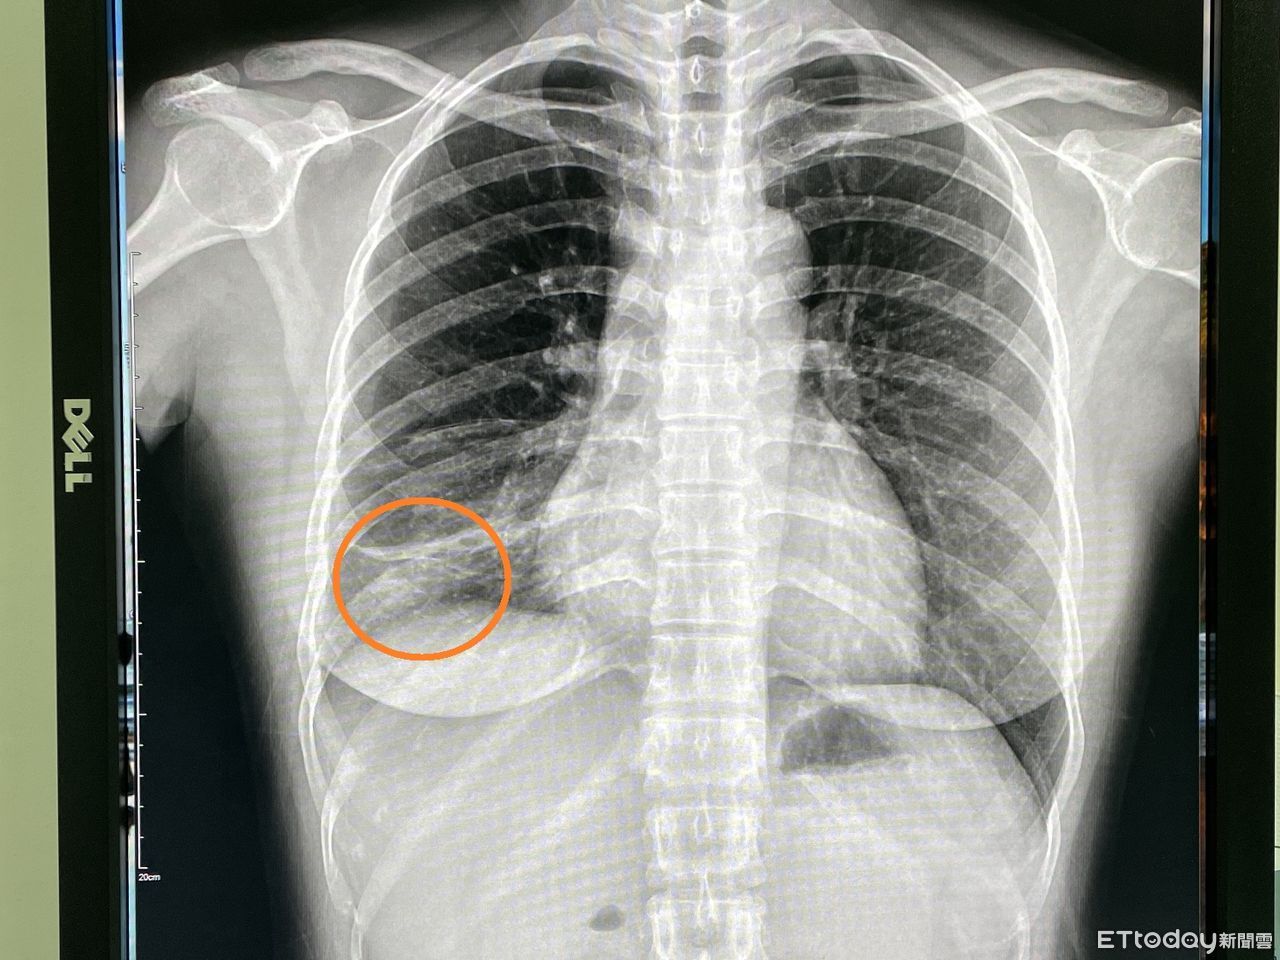

▲傳播力不輸Omicron!女作業員肺結核連咳2個月,醫驚「下肺葉塌陷了」。(圖/院方提供)

近日台灣新冠肺炎Omicron呈現急速擴大流行的趨勢,引發民眾的高度關注,然而另一種傳染性疾病也悄悄散播中。烏日林新醫院胸腔內科主治醫師許人文近日在門診發現一名32歲女作業員,已經咳嗽兩三個月不見好轉,來門診進行胸部X光檢查,發現右下肺葉有一小片扁平塌陷和浸潤的病灶,醫師竟然發現作業員痰液中佈滿了密密麻麻的肺結核菌,屬於罕見的「右下肺葉」開放性肺結核病人,醫院已進行法定傳染病通報。

根據國外文獻統計,下肺葉肺結核的病人,大多以40歲以下的年輕女性為主,肺結核的X光表現,大部分都是在兩側的上肺葉,然而在「下肺葉」的個案非常少見,常常只有零星個案被報導,也因此常常會被醫療人員所忽略,再加上肺結核具有「非立即性傳染、不易診斷」之特性,醫師初步需要先排除肺炎、肺膿瘍、或是肺癌,再進一步考慮是否為肺結核的可能性!